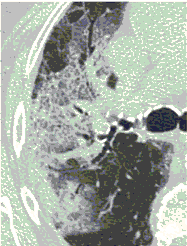

КТ имеет высокую чувствительность в выявлении изменений в легких, характерных для COVID-19. Применение КТ целесообразно для первичной оценки состояния ОГК у пациентов с тяжелыми прогрессирующими формами заболевания, а также для дифференциальной диагностики выявленных изменений и оценки динамики процесса. КТ позволяет выявить характерные изменения в легких у пациентов с COVID-19 еще до появления положительных лабораторных тестов на инфекцию с помощью МАНК. В то же время, КТ выявляет изменения легких у значительного числа пациентов с бессимптомной и легкой формами заболевания, которым не требуется госпитализация. Результаты КТ в этих случаях не влияют на тактику лечения и прогноз заболевания при наличии лабораторного подтверждения COVID-19. Поэтому массовое применение КТ для скрининга асимптомных и легких форм болезни не рекомендуется.

3. Применение лучевых методов у пациентов с симптомами ОРВИ легкой степени тяжести и стабильном состоянии пациента, возможно только по конкретным клиническим показаниям, в том числе при наличии факторов риска, при условии достаточных технических и организационных возможностей. Методом выбора в этом случае является КТ легких по стандартному протоколу без внутривенного контрастирования или РГ при ограниченной доступности КТ. Использование УЗИ в этих случаях нецелесообразно.

5. Рекомендовано проведение лучевого исследования пациентам при среднетяжелом, тяжелом и крайне тяжелом течении ОРИ с целью медицинской сортировки, оценки характера изменений в грудной полости и определения прогноза заболевания:

- выполнение КТ легких без внутривенного контрастирования в стационарных условиях или в амбулаторных - при показаниях к госпитализации;